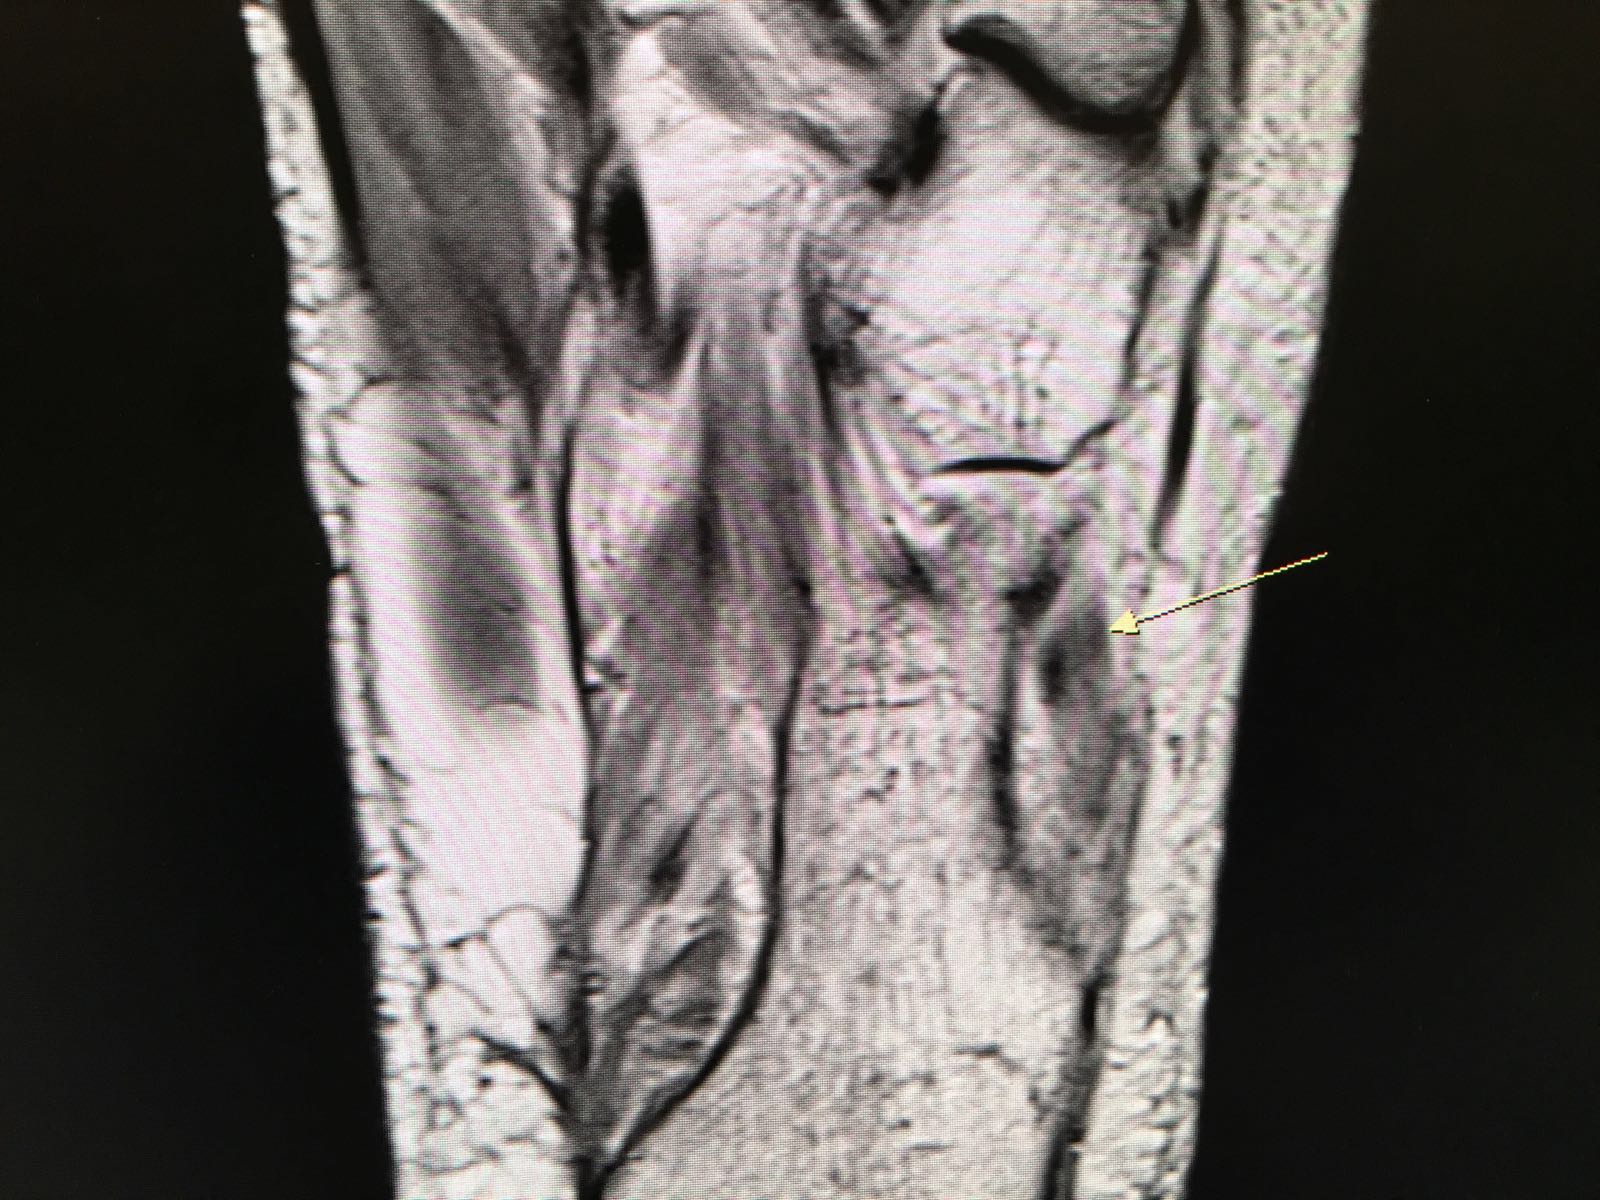

MRI of the ankle will usually delineate the diagnosis accurately.

In the case illustrated in the MRI scan here, the peroneus longus tendon distal to the lateral malleolus showed a longitudinal tendon split.